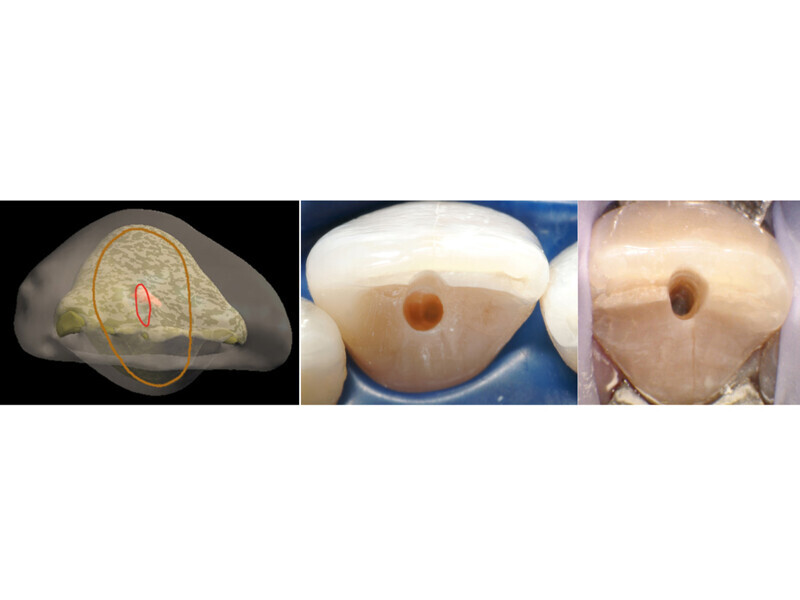

Fig. 5: In anterior teeth, the canal orifice is typically located just lingual to the incisal edge in incisors and the cusp tip in canines (middle) or directly under the incisal edge or cusp tip (right).

Fig. 6: A potential problem when attempting to access the orifice in anterior teeth is an approach at the middle of the lingual surface with an angle not following the root’s long axis that can lead to perforation of the tooth on the facial cervical (A), and the bur being used for access should be kept parallel to the roots long axis which often places the orifice under the incisal edge (B).